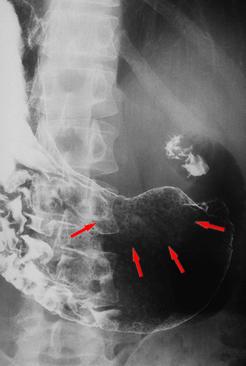

림프절전이를 동반한 위각부 소완 중심의 표면함몰형(IIc형) 조기위암

악성 상피성종양/인환세포암

위(부위)/위각

X-P

0형(표재형)/IIc형(IIc)

30~34

m